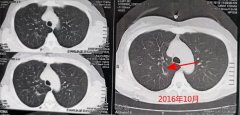

肺部结节一直是大家关注的热点话题,好好地体个检,检出颗地雷,就算可能是哑的,也总...